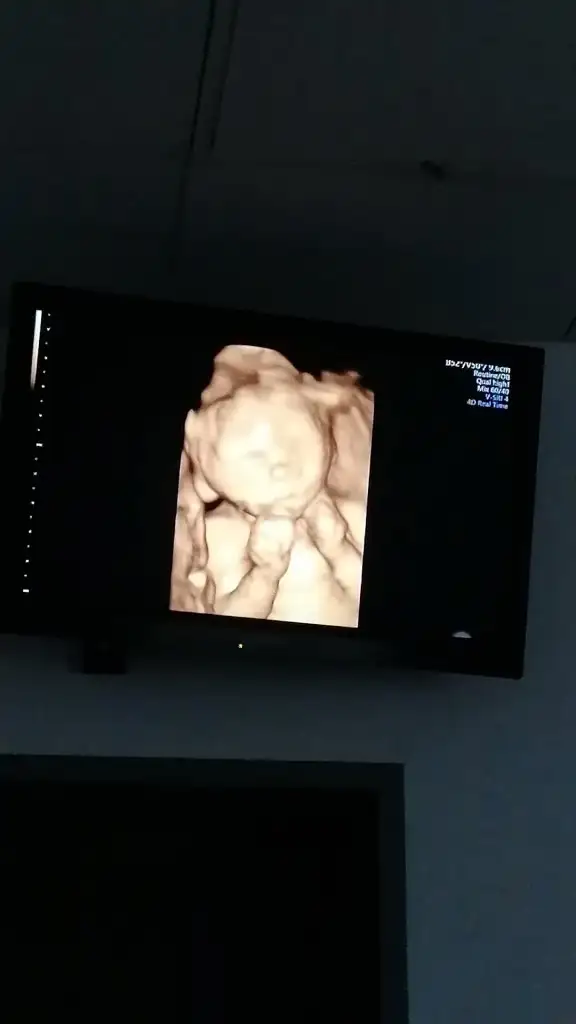

Teşekkür ederimmasallah yausg goruntusu varmi bu haftalarda nasil oluolar cok merak ediorm

masallah yausg goruntusu varmi bu haftalarda nasil oluolar cok merak ediorm

Masallah ya cok guzelEki Görüntüle 2719106

Bizim oglan bugün cok hareketliydi ac karna gittim bi yerinde durmadi sürekli birseyler yapti bu pozu hosuma gitti esim cekmisartik boydan usg görüntüsü yok. Büyüdüler sükür

Eki Görüntüle 2719113 buda bacaklari ayaklari.